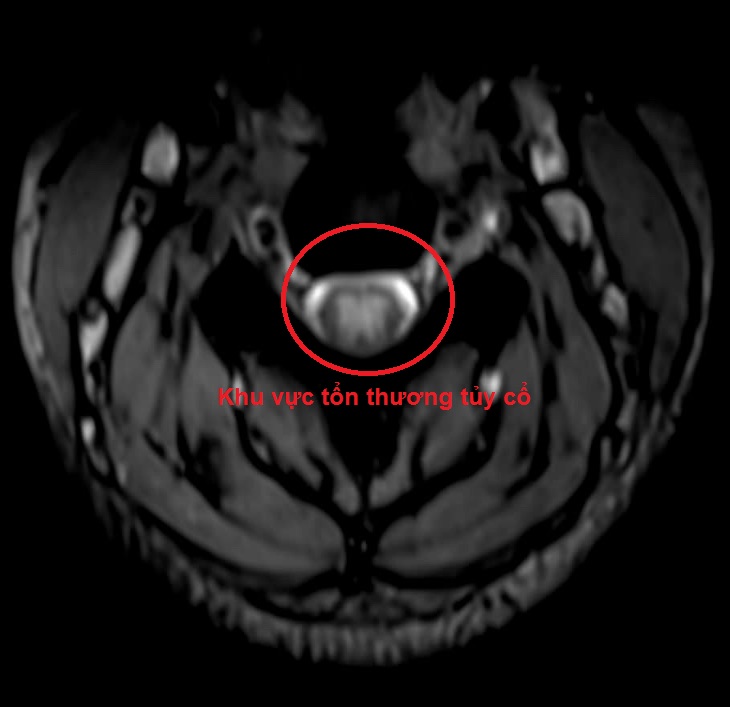

Hình ảnh tổn thương tủy cổ dẫn đến yếu liệt các chi sau khi hút 15 quả bóng cười của 1 nữ sinh ở Vĩnh Phúc. (Ảnh minh họa và BVCC).

Sau xét nghiệm, chiếu chụp bệnh nhân được chẩn đoán, tổn thương thần kinh ngoại vi giai đoạn bán cấp do lạm dụng bóng cười và được chỉ định điều trị bằng thuốc tăng dẫn truyền thần kinh, vitamin B12 liều cao. Sau 10 ngày điều trị, người bệnh đã cải thiện hơn, đi lại, vận động được, đỡ tê bì…

Chính vì vậy, trên những người bệnh có triệu chứng tê bì, dị cảm tứ chi, việc khai thác tiền sử lạm dụng bóng cười, khám lâm sàng và cận lâm sàng đầy đủ, đặc biệt là MRI cột sống cổ và đo dẫn truyền thần kinh sẽ giúp cho việc chẩn đoán chính xác, từ đó sẽ phục hồi chức năng vận động của người bệnh một cách tối đa.